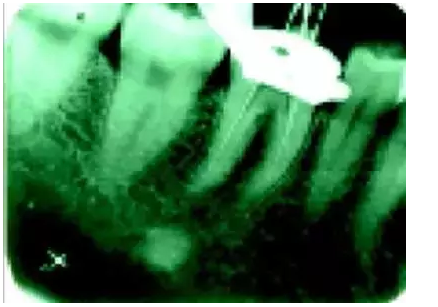

1)尋找遺漏根管

2)根管系統(tǒng)的解剖形態(tài)是極其復雜的。牙髓病學教材中常常提到磨牙有三個根管,前磨牙兩個根管,前牙一個根管。實際上,根管系統(tǒng)并不是如此可預知的,而是常常存在許多解剖變異。根管系統(tǒng)的解剖形態(tài)學研究發(fā)現(xiàn):幾乎50%磨牙中(上頜和下頜)有第四根管存在,30%以上的前磨牙有第三根管,接近25%的前牙有雙根管。

在傳統(tǒng)的根管治療中,開髓后往往只是依靠術(shù)者的視覺和經(jīng)驗去尋找根管,所以常常存在遺漏根管的可能,從而導致根管治療的失敗。研究發(fā)現(xiàn),X線片上顯示根管充填滿意的患牙仍有癥狀的主要原因是有遺漏的根管未治療。

所以對于經(jīng)過完善根管治療后的牙,如果出現(xiàn)持續(xù)疼痛,首先應該考慮可能有遺漏根管的可能。

手術(shù)顯微鏡是用于尋找隱藏或遺漏的根管最重要的工具。因為手術(shù)顯微鏡能夠幫助醫(yī)生觀察到肉眼或普通放大鏡無法分辨的根管口和微小病損。在手術(shù)顯微鏡下,利用高倍數(shù)(16~24倍)的放大作用以及理想的照明條件,仔細檢查患牙的髓室底,許多細微的解剖結(jié)構(gòu)能容易被發(fā)現(xiàn)。

為了光線能充分進入髓腔,髓室頂應完全揭去,開髓口的形態(tài)應根據(jù)具體牙位進行適當修改,使得所有根管口都能夠充分暴露。同時,對髓底進行美藍染色也有助于根管口和微小病損的識別。

對于有些牙根管在根管口下3~5毫米處分叉以及近頰和遠頰根管口非常接近的上頜第二磨牙,手術(shù)顯微鏡更是相當有價值的工具。因為根管的分叉點和獨立的根管口能清楚地在顯微鏡下被觀察到。